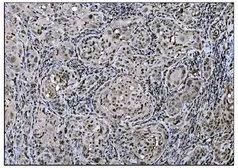

NP_006723

Images